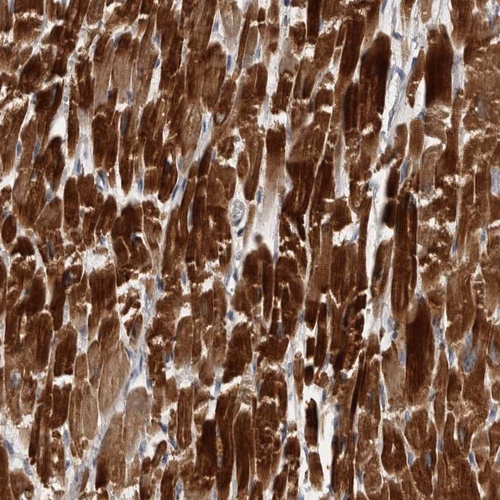

Immunohistochemical staining of human heart muscle shows strong cytoplasmic positivity in myocytes.